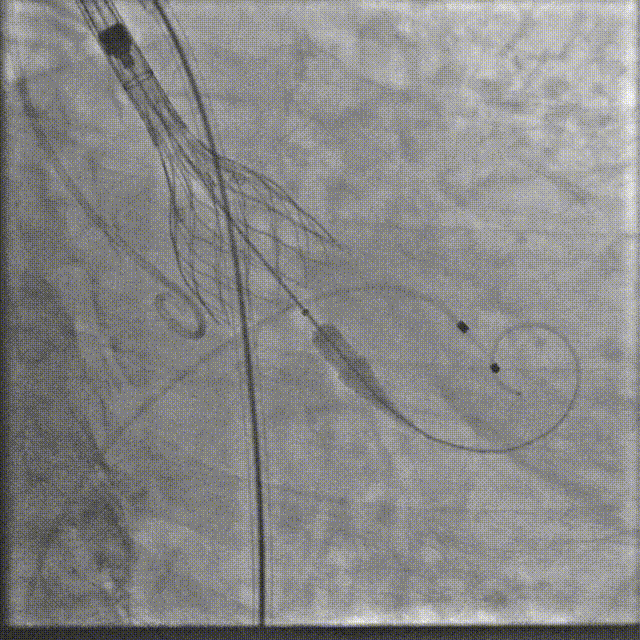

瓣膜系统过弓

定位造影

瓣膜确认位置后释放

回收极限处造影

最终造影

术后复查造影示瓣膜位置满意,形态良好,冠脉显影良好;TTE示轻微瓣周漏;排除入路血管问题,手术圆满成功。